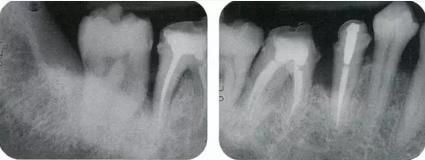

360截圖20170422102020512.jpg

▲圖11-1,2

▲圖11-1,2  術(shù)前的X光片、右下6,7之間存在牙根接近,并存在10mm的牙周袋。